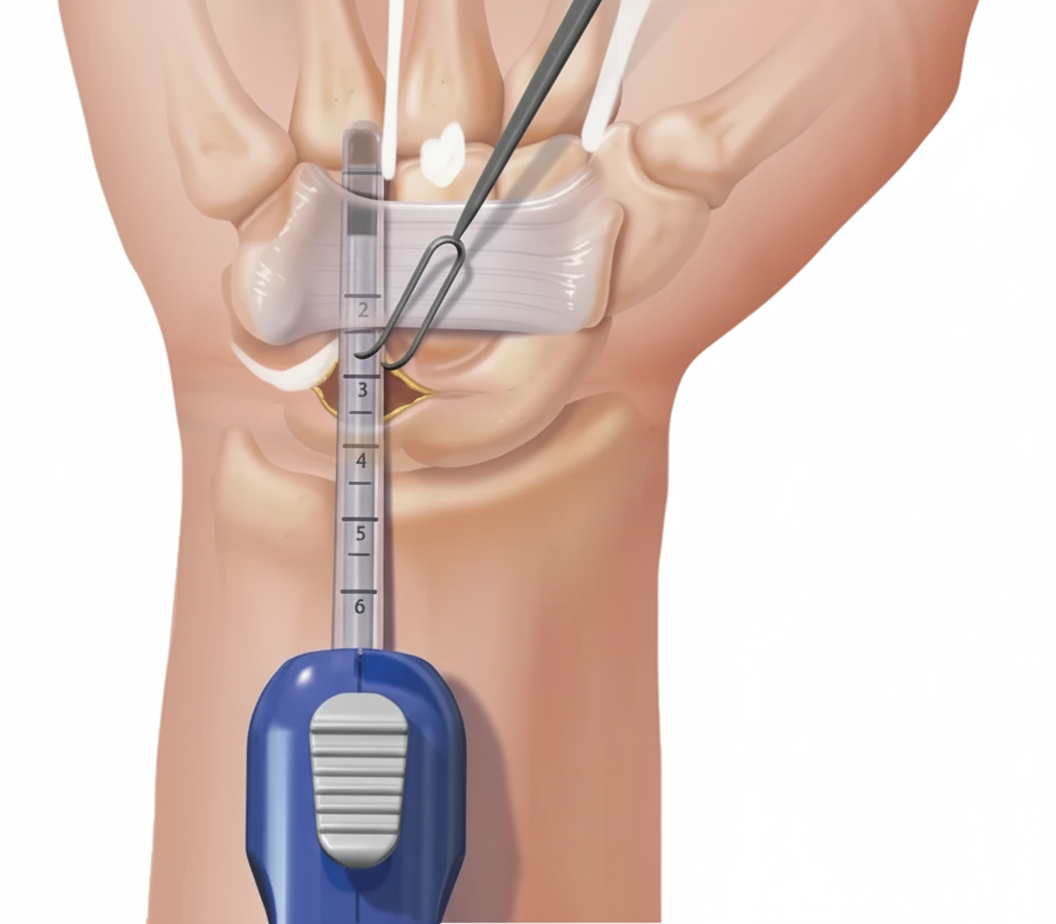

Ofrecemos un tratamiento de vanguardia para el túnel carpiano mediante cirugía endoscópica. Esta técnica mínimamente invasiva permite una recuperación más rápida y menos dolorosa, minimizando las cicatrices y permitiéndote volver a tus actividades diarias en poco tiempo.